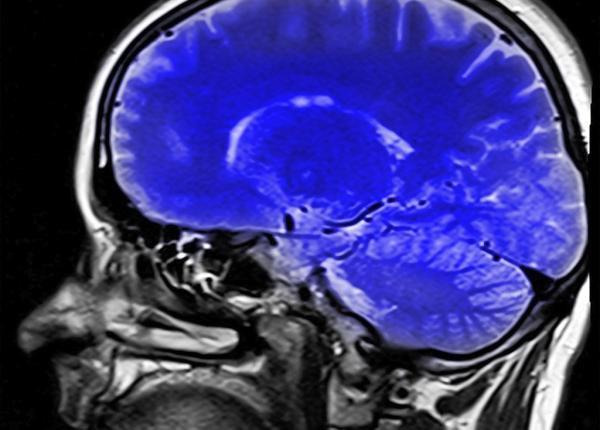

Îmbătrânirea. Cum se modifică creierul pe măsură ce trece timpul